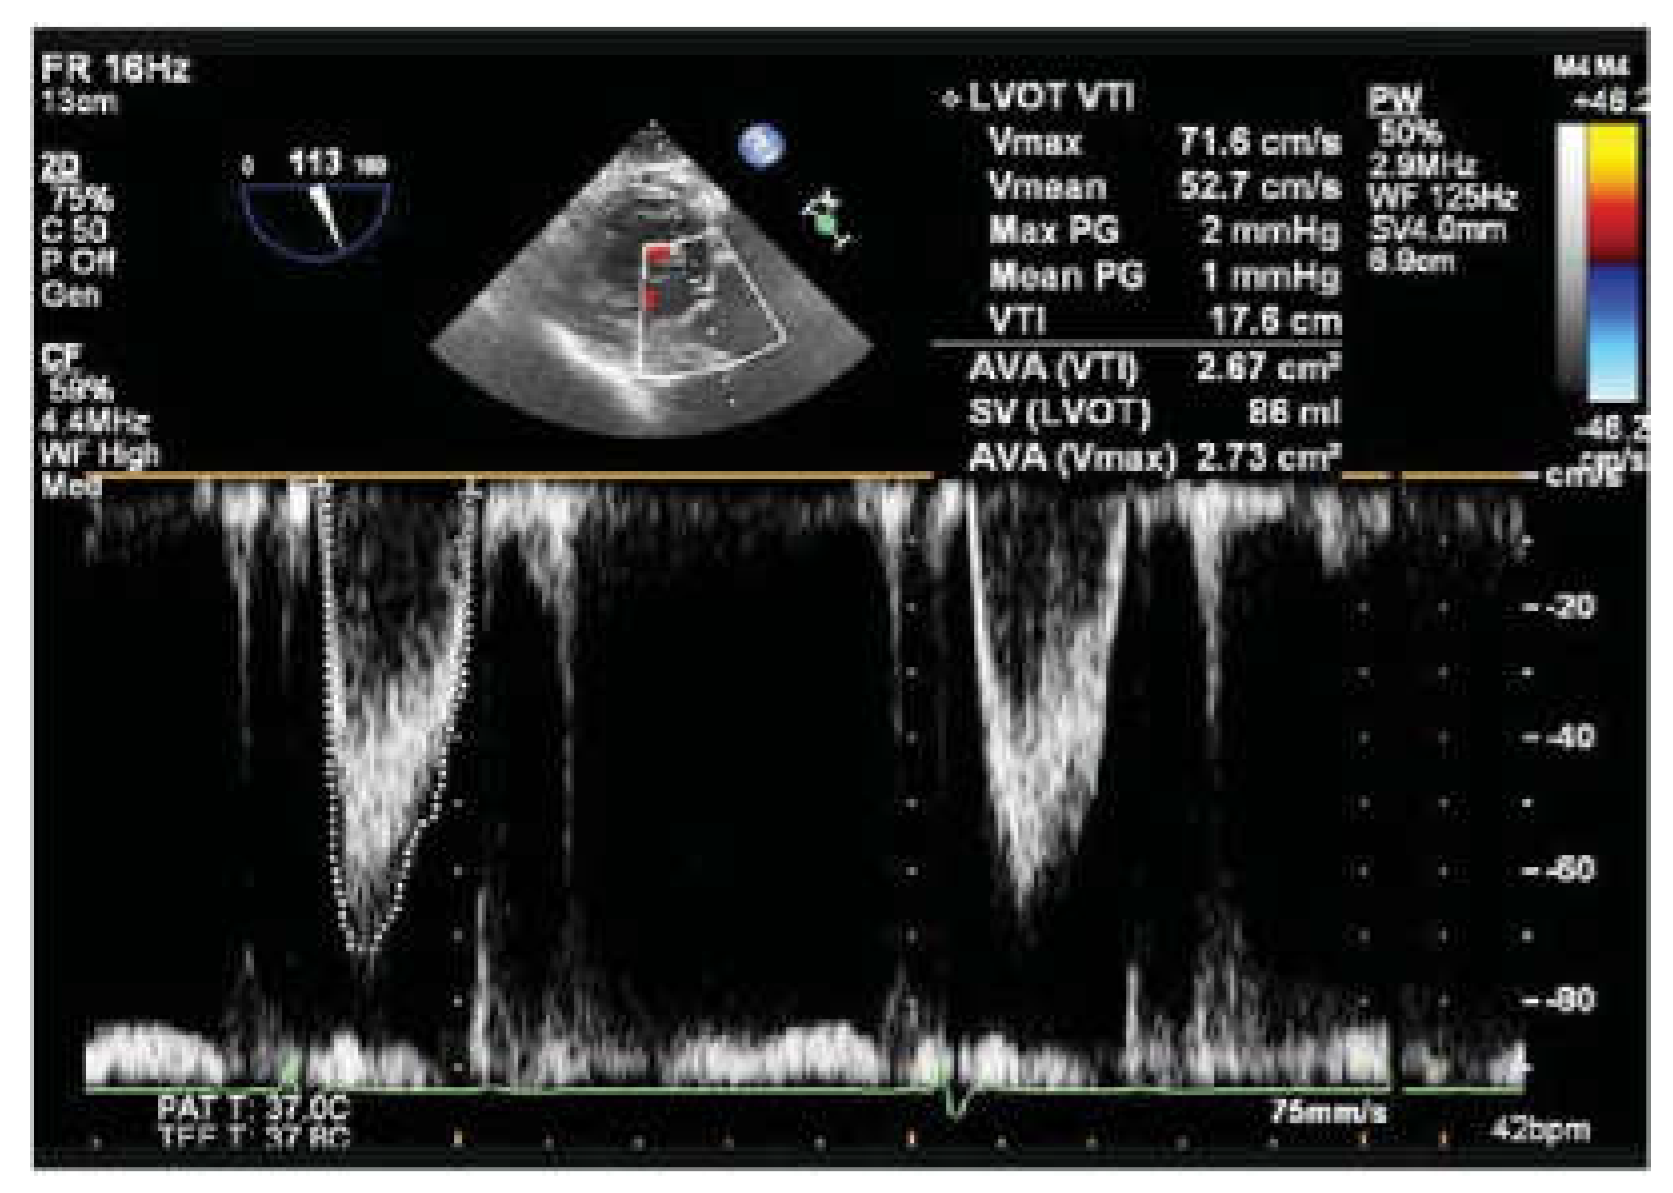

Step 3 d Timing of the LV and RV goal is to decrease mitral regurgitation and increase LVOT integral. Evaluate LVOT integral adjust LV/RV timing to maximize LVOT integral and reduce mitral ERO. The RV LV timing delay is chosen by iteration of interval to optimize LVOT VTI. Figure 4

Figure 4.

LVOT Integral and Mitral regurgitation ERO.